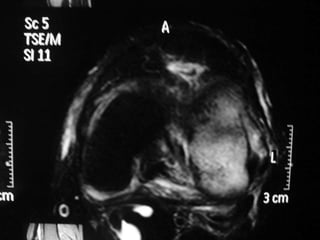

The document presents a detailed case study of a patient with transient osteoporosis of the hip (TOH) and spontaneous osteonecrosis of the knee (SONK) treated at Choithram Hospital & Research Centre in India. Over 20 years, the patient experienced multiple episodes of TOH and SONK with no history of trauma or co-morbidities, resulting in resolutions and recurrences of conditions. The information is intended for orthopedic surgery students and highlights personal experiences and case collections, with a disclaimer regarding content usage and potential controversies.